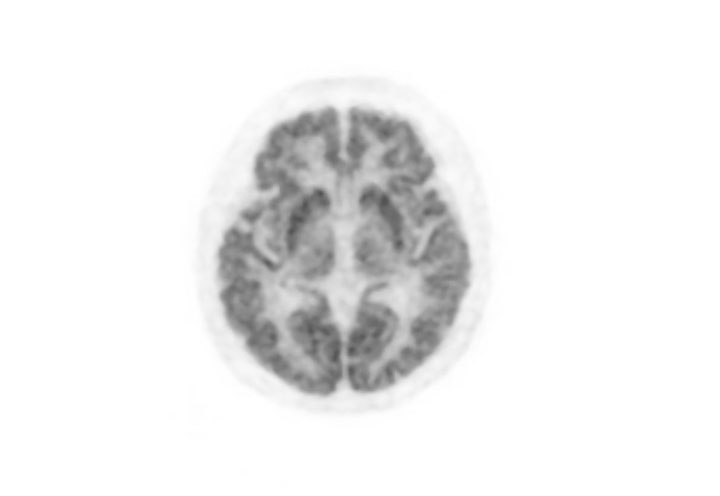

Head / Case3 : FDG

Axial

Courtesy : Kindai University Hospital

- Imaging protocol

- Injected dose: 4.49 MBq/kg, 18F-FDG

- Uptake time: 46 minutes

- Scan time: 30 minutes